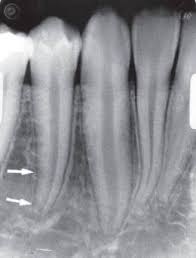

Trong đó, kĩ thuật phân giác cho vùng răng nanh hàm dưới là một trong những phương pháp chụp phim cận chóp thông dụng trong nha khoa. Phương pháp này cho phép bác sĩ nha khoa tạo ra hình ảnh rõ ràng về các răng và xương hàm trong vùng này, đặc biệt là trong trường hợp các răng xếp chồng lên nhau hoặc khó tiếp cận.

Bước 1: Kiểm tra tư thế đầu, khớp cắn hoặc những vùng có bất thường khác.

Bước 2: Cầm phim bằng ngón trỏ hoặc ngón cái ở cạnh ngắn của phim. Đặt phim nằm dọc sao cho cạnh trên của nó cao hơn rìa cắn răng nanh 6mm. Nếu gặp phải sự kháng cự thì bảo bệnh nhân nâng lưỡi lên sau đó để lưỡi thư giãn.

Bước 3: Hướng dẫn bệnh nhân giữ phim bằng ngón trỏ bằng cách ấn nhẹ lên phim. Kê một miếng bông giữa phim và răng để tránh cong phim cọ sát vào cung răng gây đau.

Bước 4: Đặt góc ngang của tia trung tâm đi qua kẽ răng nanh hàm dưới và răng hàm nhỏ thứ nhất hàm dưới.

Bước 5: Đặt góc đứng khoảng -20 độ.

Bước 6: Điểm vào của tia trung tâm là giữa chân răng nanh, khoảng 2,5cm trên bờ nền xương hàm dưới. Xác định đường này bằng cách hạ một đường từ chân cánh mũi xuống cắt đường nối đỉnh cằm đến chân dái tai, đấy chính là điểm vào để chụp răng nanh.